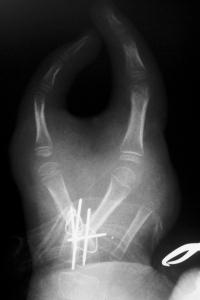

Closeup of fixation: crossed K wires augmented with interosseous wires. The stretched bifurcation of the common digital artery to the adjacent sides of the digits can be seen at the distal upper end of the image behind the retractor.